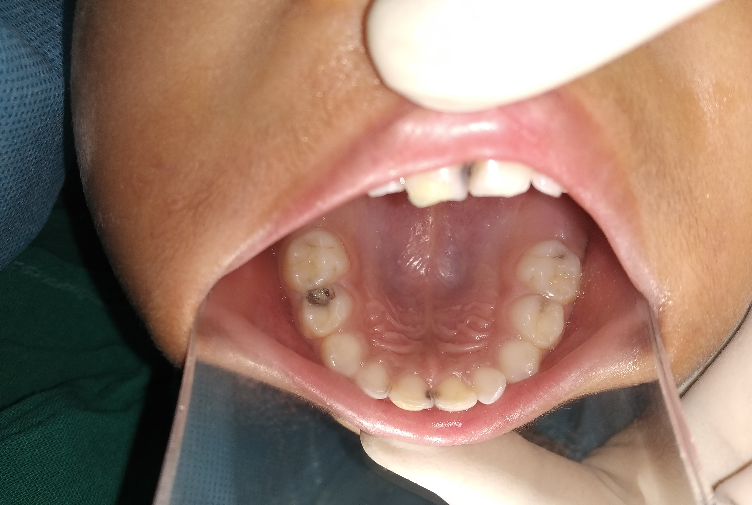

SDF solution (38%) should be applied directly over the dried carious lesions using a micro brush. Minimum but adequate amount of the solution is used cautiously to prevent inadvertent gingival discoloration. No more than one drop of 38% SDF solution is recommended in one visit. [[Figure 2]] [[Figure 3]] It is ideally recommended to remove the excess SDF using cotton pellets/ gauze, after leaving one to three minutes in contact.[34]

Follow-up

Follow up visit is recommended after 2-4 weeks of the first application of SDF to check the efficacy of the procedure done. [[Figure 4]] If the lesions do not show features of an arrested site (Dark brown color, hard texture), reapplication is indicated.[38]